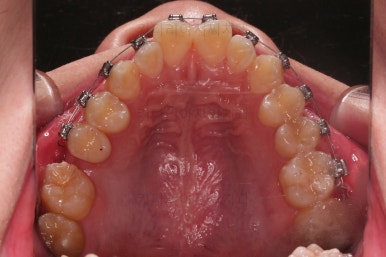

우선 브라켓을 부착했고요.

이번에 환자분이 선택하신 장치는 엠파워 메탈이라고 하는 자가결찰 금속장치인데요.

메탈이라고 다 구형의 장치는 아니고 "자가결찰"인지 여부가 굉장히 중요해요.

윗니는 가지런하게 하면서 아랫니는 초기 단계부터 뒤로 밀어주게 됩니다.